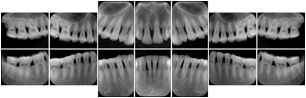

2. A patient requests cosmetic surgery to enhance their facial appearance. The case requires consultation between an orthodontist in New York and an oral surgeon in California. The cephalometric series of 2D projections constructed from a volumetric CT data set that is used for the discussion is arranged by a Structured Display for transfer between the two practitioners.

Cephalometric Series Structured Display

Figure OO-2. Cephalometric Series Structured Display